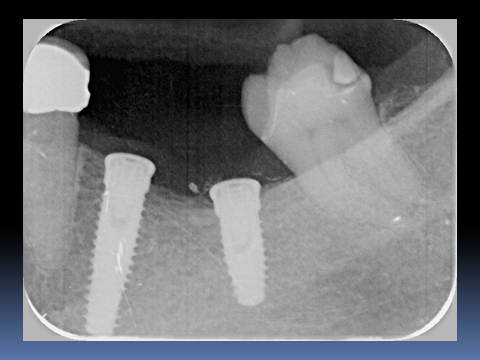

この患者様は、右上の奥歯の歯茎から出血してくるとのことで来院されました。歯周組織検査とレントゲンで診断を行った結果、重度の歯槽膿漏が認められ、保存不可能の為、抜歯になると伝えたところ、入れ歯は絶対に嫌だと言われたので、インプラント治療となりました。CT撮影を行ったところ、上顎洞底までの距離が3ミリ程度しかなかったのですが、骨が固く、フィクスチャーの一次固定が良好だったので、開窓法による上顎洞底挙上術とフィクスチャーの埋入を同時に行いました。約10カ月後に二次手術を行い、上部構造をセットしました。また、右下の臼歯部のブリッジにも大きな二次カリエスが認められ、7番の遠心根が抜歯になり、6番、7番にインプラント治療をしました。